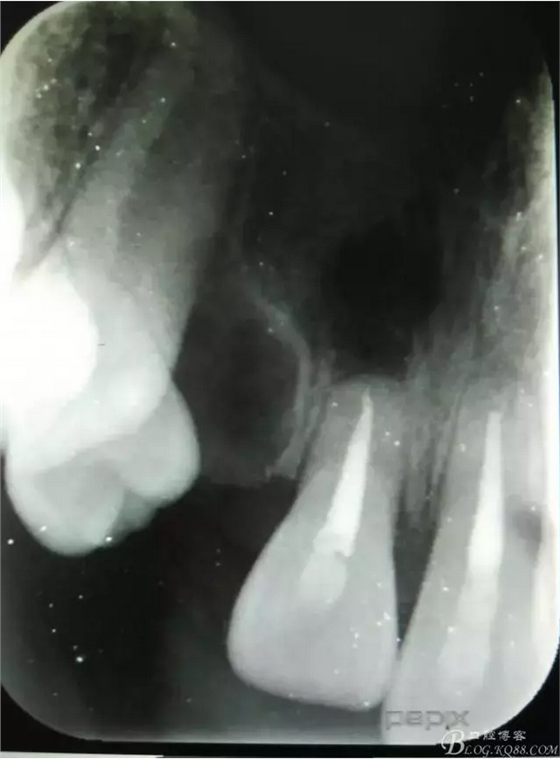

患者、李xx、男、15歲,主訴:牙不齊,矯正牙齒。??茩z查:發(fā)現(xiàn)11、21根尖三分之一折斷,患者否認(rèn)有外傷史。正畸科治療建議如圖1.。術(shù)前簽手術(shù)同意書。